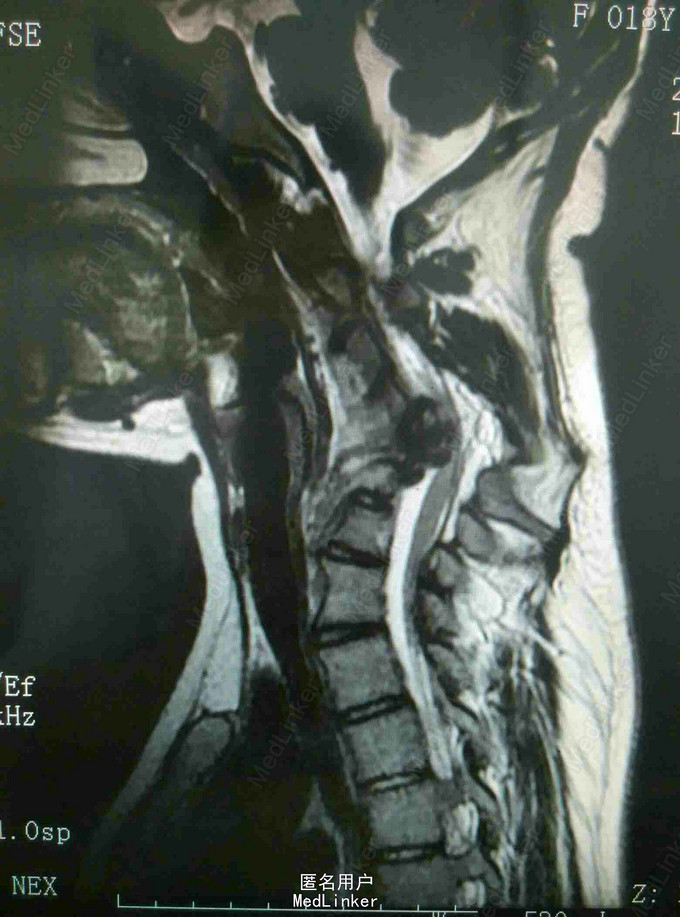

颈肩痛伴左侧肢体无力5月 患者青年男性,无明显诱因出现颈肩痛,性质钝痛,伴有左侧肢体无力,症状反复发作五月。于当地医院就诊查核磁提示颈椎结核,椎旁脓肿。患者二便正常,既往结核病史。

查体:颈椎生理弯曲消失,各棘突及椎旁压痛,胸腰椎生理弯曲不在,各棘突无压痛,椎旁无叩击痛。左侧肢体肌力降低,双侧Hoffoman征阳性,Babinski征阳性。 辅查:我院磁共振提示颈椎结核并椎旁脓肿,颈椎失稳。

诊断:颈椎结核伴椎旁脓肿 颈椎不稳 四肢不全瘫。 治疗:颈前路病灶清除植骨融合内固定术+Halos架固定,术后护肝抗结核治疗